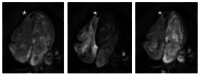

Figure 4. First-pass perfusion (FPP) imaging

First-pass perfusion (FPP) imaging during the acute phase reveals an intracavitary low signal mass with no contrast uptake (white stars), indicative of a thrombus